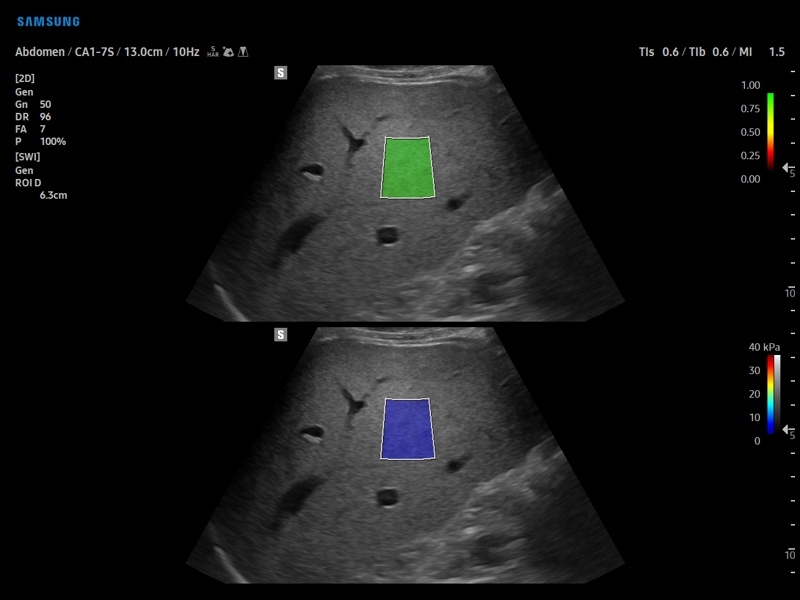

• Модуль S-Shearwave imaging – программа цветовой сдвиговой эластографии позволяющая автоматически определять индекс жесткости различных участков исследуемого объекта в кПа или м/с, получая при это еще и индекс достоверности данных RMI.